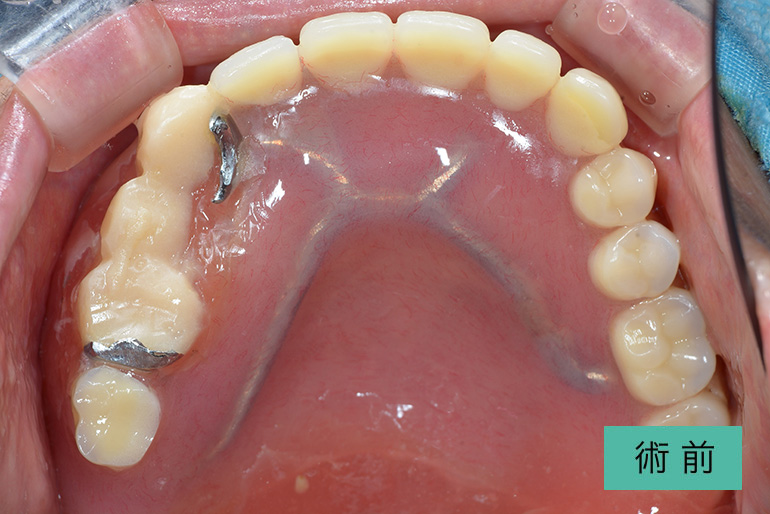

上顎総インプラント

| 治療内容 | 両側サイナスリフト(上顎洞底挙上骨造成術)し、上顎総インプラント治療を行った |

|---|---|

| 治療期間・回数 | 1年9ヶ月、29回(他部位の治療を含む) |

| 費用(税込) | ¥4,935,000 ※自由診療 |

| リスク・副作用 | 疼痛、腫脹、出血、鼻血、青痣、補綴の脱落、インプラント周囲炎、神経麻痺 |